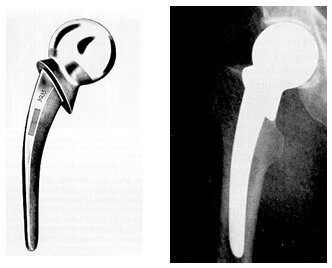

• Primer reemplazo total de cadera

Primer reemplazo total de cadera

Hecha por médicos británicos

• Prótesis de partes cambiantes

Prótesis de partes cambiantes

Willians Harris desarrolla un equipamiento para medir la presión real a la que es sometida una cadera funcional. Se introduce el sistema modular de reemplazo de cadera